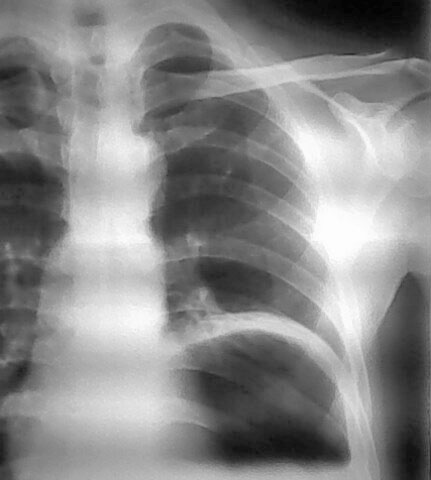

男.55.咳嗽数天

左侧膈肌抬高,其胸腔可见胃泡影,提示膈疝,建议钡餐或ct检查。

壁厚,应该是胃底+膈;有宽大液平面,无肠皱壁,应该是胃腔而不是膈疝或结肠间位;支持膈膨升。

膈膨升与膈疝是两回事,应进一步检查。

膈疝膈肌位置不上升,胃肠位置上移进入胸腔,膈肌动度正常或受限。

膈膨升膈肌位置显著上升,膈肌动度减弱、消失或出现矛盾运动,胃肠位置位于膈下。另外膈麻痹病人膈肌位置也有上升。应注意鉴别。

考虑左侧膈膨升,膈疝待排。